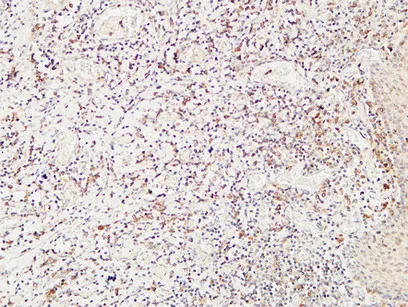

CD244 Rabbit Polyclonal Antibody

Cat: APRab08306

Size1:50μl Price1:$118

Size2:100μl Price2:$220

Size3:500μl Price3:$980

Size2:100μl Price2:$220

Size3:500μl Price3:$980